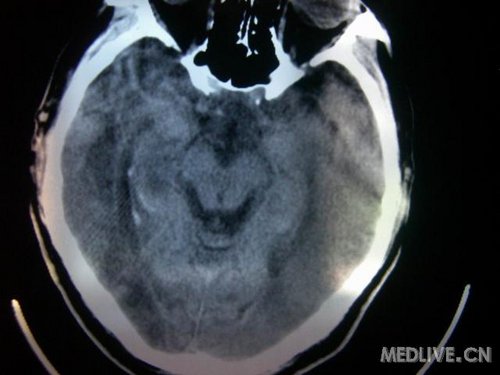

病人男性 73岁 市民 以“幻听、幻视两天,言语含糊、精神错乱一天”入院。

两天前无诱因出现幻听、幻视,描素眼前有彩色的圆圈,听见有人说话(但说什么不详),一天前出现胡言乱语,言语含糊,精神错乱,问话不答,行走略有不稳,来我院就诊,门诊头CT检查:(下面有片)入院后查体不合作,表情淡漠,问话不答,大致检查了一下,颅神经未见明显异常,颈软,右手活动似忽略差。其他检查不配合。脑电图:广泛轻-中度异常。

既往史:半年前曾患“右侧脑梗塞”但无明显后遗症,生活能自理,无高血压、糖尿病、心脏病史。

此次入院时的片子: